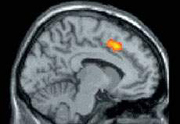

Ученые установили, почему болит душа

Душевная боль каким-либо образом отвергнутого обществом человека воспринимается мозгом так же, как и боль физическая.

Ученые из Университета Калифорнии в Лос-Анджелесе под руководством Наоми Эйзенбергер (Naomi I. Eisenberger) проверяли свою гипотезу в эксперименте. Добровольцы играли в компьютерную игру, будучи уверенными, что в ней принимают участие трое человек. На определенном этапе оказывалось, что два других игрока игнорируют участника, исключая его из игры. При этом регистрировалась активность головного мозга.

Когда человек понимал, что его отвергли, регистрировалась реакция в передней поясной коре – участке головного мозга, который отвечает и за восприятие физической боли. По словам Эйзенбергер, данные исследования дают основание полагать, что социальное исключение любого вида, например, развод или отказ прийти на свидание, сопровождается болевой реакцией в передней поясной извилине.

По мнению ученых, восприятие одиночества как физической боли появилось как защитная реакция. "Так как период детства, когда человек нуждается в заботе, длиться очень долго, важно оставаться в социальной группе. В противном случае мы не выживем, - говорит Эйзенбергер. – Гипотеза заключается в том, что система привязанности к обществу, которая удерживает человека в группе, взаимодействует с болевой системой ради выживания вида".